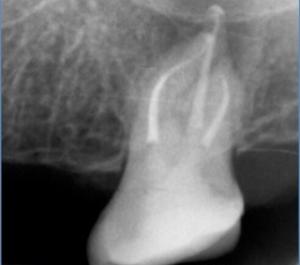

Root canal treatment is required when the pulp of the tooth has been damaged. A number of conditions can lead to the irreversible damage of the pulp; decay, deep fillings, trauma, tooth fracture, infection. Sometimes there is no apparent cause. The only option to root canal therapy is the extraction of the tooth.